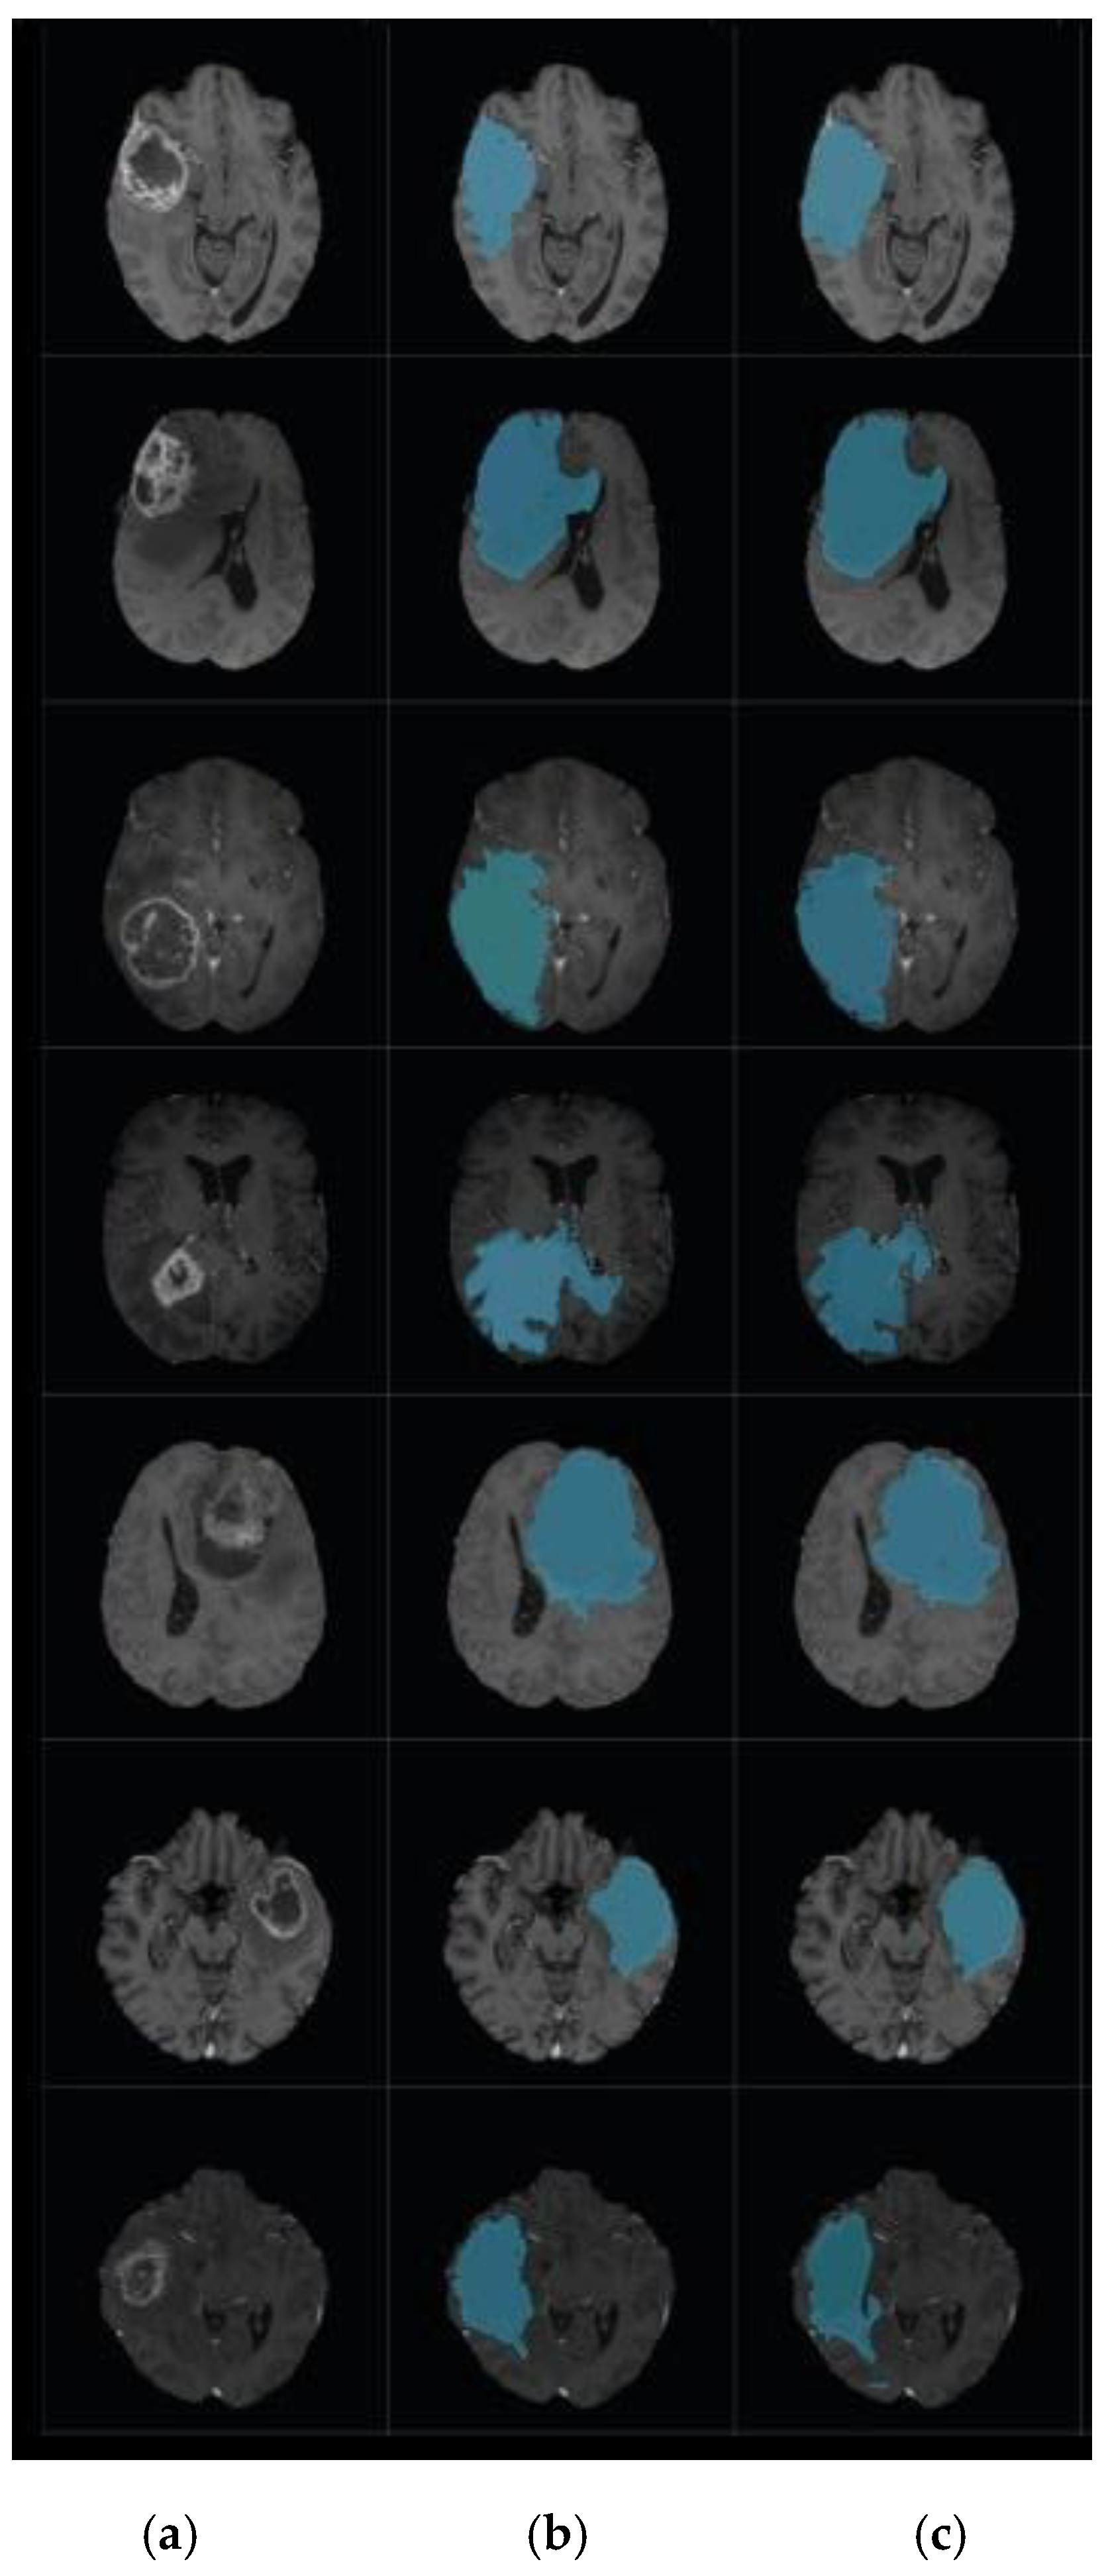

Another group of experiments was carried out to compare the efficiency of the combination of DA clustering and the level set algorithm in the field of brain tumor segmentation with a combination of some nature-inspired metaheuristic algorithms with level set. We replaced the DA module in the proposed model with well-known metaheuristic modules, via a BlackBox, with their default configurations. These metaheuristic algorithms include Particle Swarm Optimization (PSO), the Artificial Bee Colony (ABC) Algorithm, and the Clown Fish (CF) Algorithm [33]. The results in Table 3 confirm the research hypothesis that using the DA classifier based on accurate center points extracted using k-means will enhance the segmentation accuracy. The suggested combination achieved a 1% increase in accuracy compared to the nearest combination that shields between the CF and the level set segmentation. In PSO, ABC, and CF, the convergence rate is affected by the main parameters that affect the individual’s movement toward the best position obtained thus far by individuals and others in the group; this consequently affects their tendency to be explorative or exploitative. In DA, the convergence rate is not affected by any parameters. DA tends to be explorative, which is shown by the lowest convergence rate the compared methods. In a comparison of the time taken, PSO, ABC, and CF took about 95–100 s, whereas DA took about 40–45 s to complete the segmentation process. Figure 9 shows a sample of segmentation results using DA and CF combined with level set segmentation.

Figure 9.

Brain tumor segmentation. (a) 2D slice. (b) Final segmentation based on the Dragonfly Algorithm (DA). (c) Final segmentation based on the Clown Fish (CF) Algorithm.